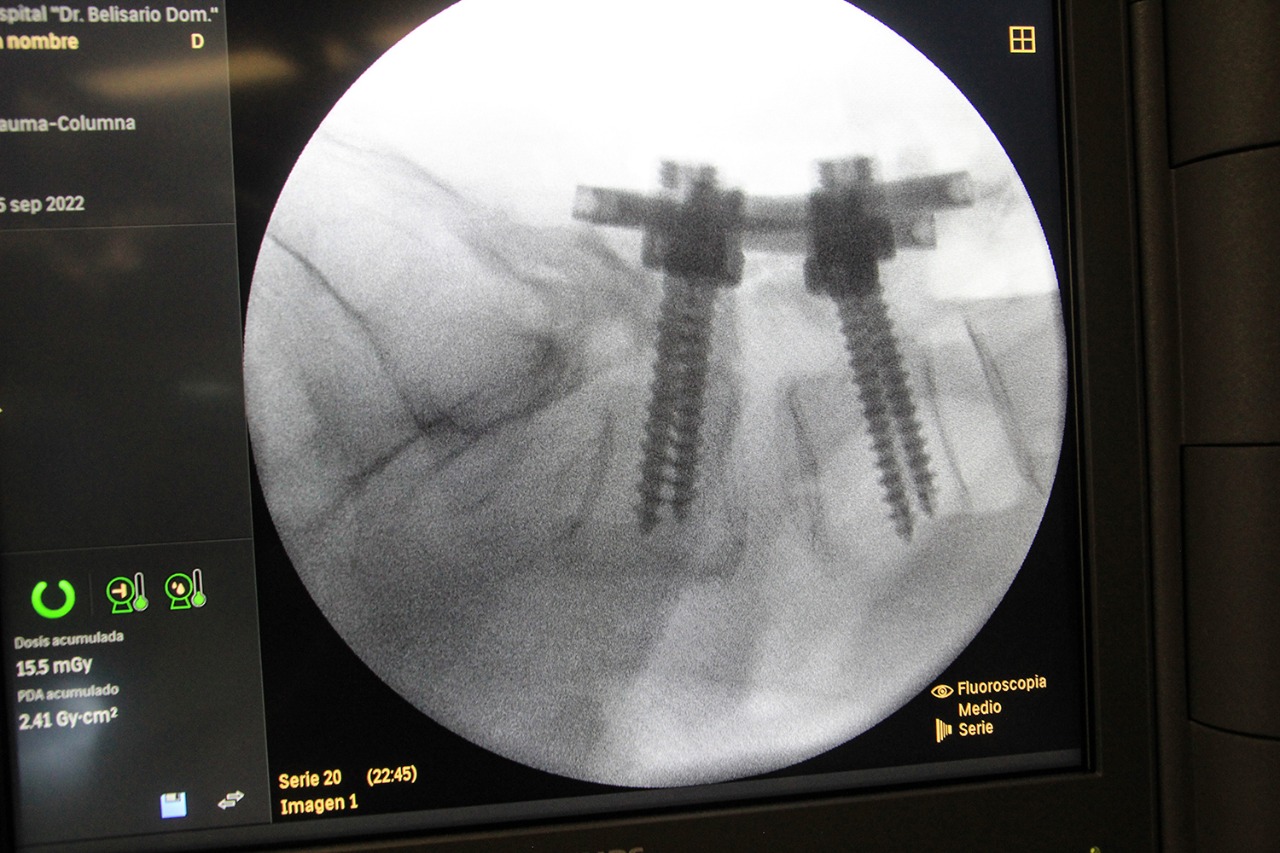

En seis meses, de mayo a noviembre de 2022, se llevaron a cabo cuatro mil 201 cirugías en 43 centros hospitalarios a derechohabientes que requerían estas intervenciones para tratar diversos padecimientos, según consta en el informe de acciones que rindió el director normativo de Salud, Ramiro López Elizalde,